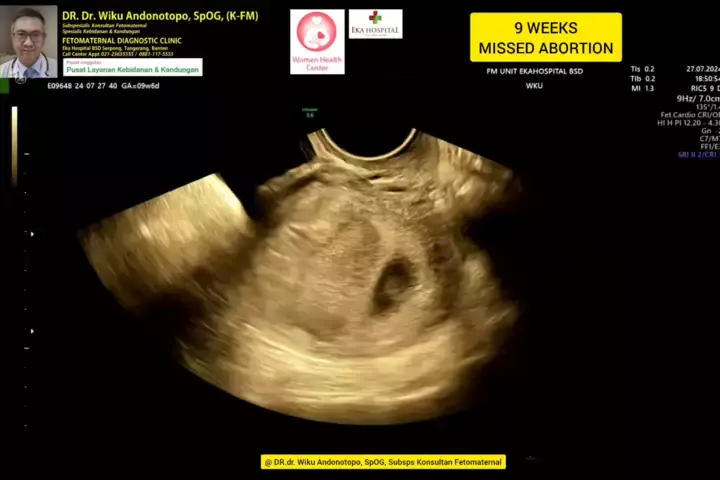

9 weeks Missed Abortion... #skriningkehamilan #drwikuandonotopo #drwiku_andonotopo #polikandunganekahospitalbsd #ekahospitalbsd #ekahospitalcibubur #ekahospitalpekanbaru #ekahospitalbekasi #rsiafamilypluit #grandfamilypik #usgkehamilansehat #usgkehamilan #usg4d #usg4dimensi #fetomaternal #usgfetomaternal #konsultanfetomaternal #fetomaternalpontianak #fetomaternalekahospitalbsd #fetomaternaljakarta #fetomaternalserpong #fetomaternaltangerang #fetomaternalmedan #fetomaternalpalembang #fetomaterna...